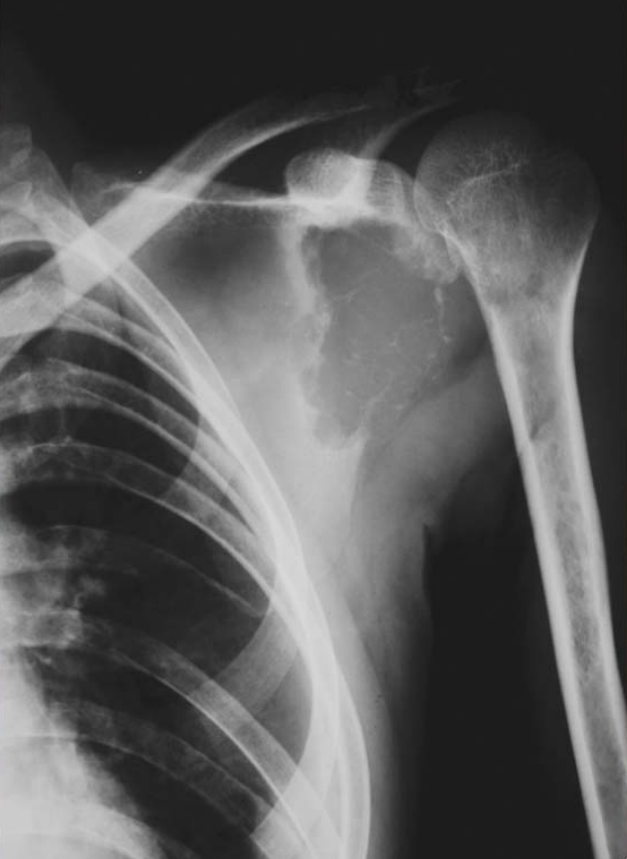

Figure2